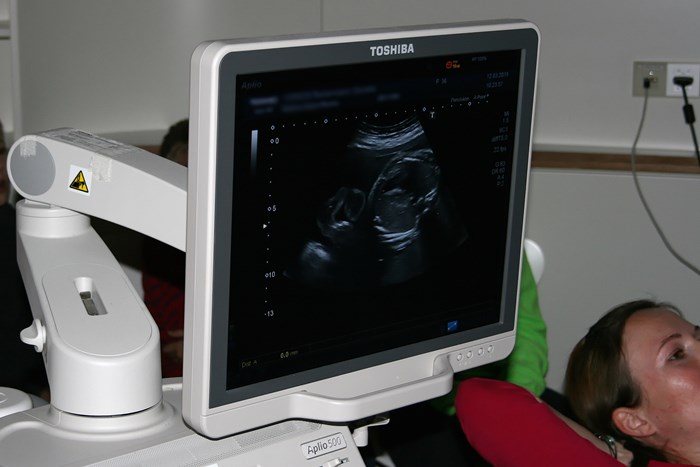

„Dürfen wir auch bei einer echten Geburt zusehen?" Adrian und seine Klassenkameraden sind an diesem Morgen mächtig aufgeregt. „Eine Entbindung zeige ich euch nicht, dafür schauen wir uns aber gleich mit dem Ultraschallgerät das ungeborene Baby unserer Patientin Daniela Reinermann an", erklärt Dr. Fröhlich den Kindern. „Vielleicht findet ihr ja auch sogar das Geschlecht heraus."

Die Schüler waren sehr gut vorbereitet und Dank moderner Technik erkannten alle die einzelnen Körperteile von Kopf bis Fuß blitzschnell. Auch die inneren Organe wie Leber, Nieren und Rippen waren deutlich auf dem großen Bildschirm zu sehen. „Wow, das Herz schlägt aber ganz schön schnell", meint Finn. „Sieh' mal Justus, ich kann sogar schon sehen, was es wird! Das ist doch eindeutig!" Und auch ihre Mitschüler nicken zustimmend.